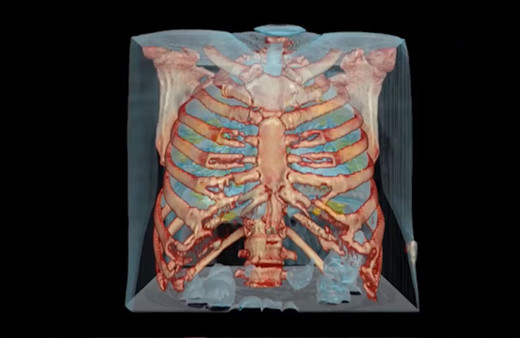

Akciğer